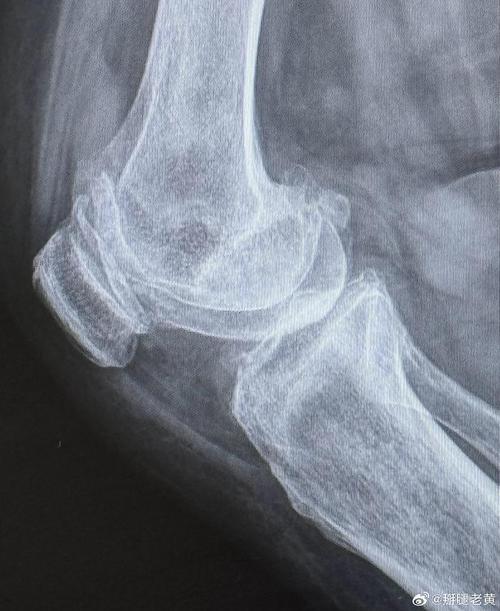

X线是RA最基础、最常用的影像学检查方法,主要评估骨与软骨的破坏情况,RA的X线改变是一个动态发展的过程,国际通用的评估标准是Sharp/van der Heijde评分系统,它从侵蚀和关节间隙狭窄两个方面量化关节损害。

中晚期RA(出现特征性破坏性改变)

骨侵蚀:

(图片来源网络,侵删)- 定义:关节边缘和邻近骨皮质出现的虫噬状、穿凿样骨质缺损。

- 特点:侵蚀灶通常位于关节边缘,与关节软骨相邻,这是滑膜血管翳从关节边缘向骨内侵袭的直接证据,典型的侵蚀形态是“穿凿样”,边缘清晰,可有硬化边。